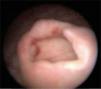

Se hospitalizó para manejo médico con antibiótico, antiespasmódico, anticolinérgico y para realizar urotomografía, el cual demostró ureterocele gigante derecho sin alteraciones anatómicas anexas a esta enfermedad. La paciente evolucionó satisfactoriamente, por lo que fue egresada con su sonda Foley, y 8 días después se realizó cistoscopia encontrando destechamiento isquémico de la pared anterior del ureterocele derecho (fig. 2), uréter contralateral normal (fig. 3) y reflujo vesicoureteral grado IV derecho que fue corroborado por cistograma miccional (figs. 4 y 5), se le realizó reimplante ureteral derecho tipo Cohen, con colocación de catéter doble-J ipsilateral, y un mes después se retiró dicho catéter. La paciente a los 3 meses se encontraba asintomática, y el cultivo y examen general de orina eran normales.